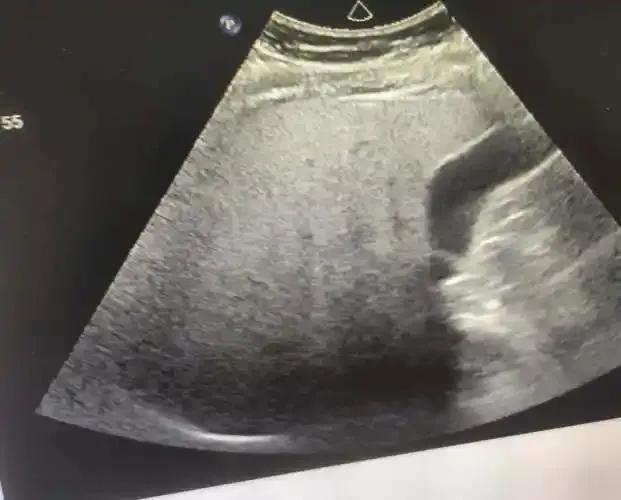

2、腹部超声:通过观察肝脏大小、形态、回声变化,判断肝实质弥漫性改变情况,还可发现有无腹水、脾大等并发症。